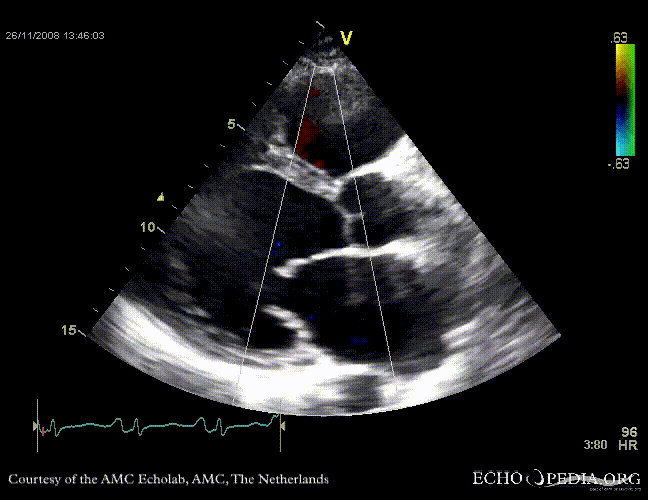

Dilated cardiomyopathy with severe mitral valve regurgitation

Courtesy of: J. Vleugels, AMC, The Netherlands